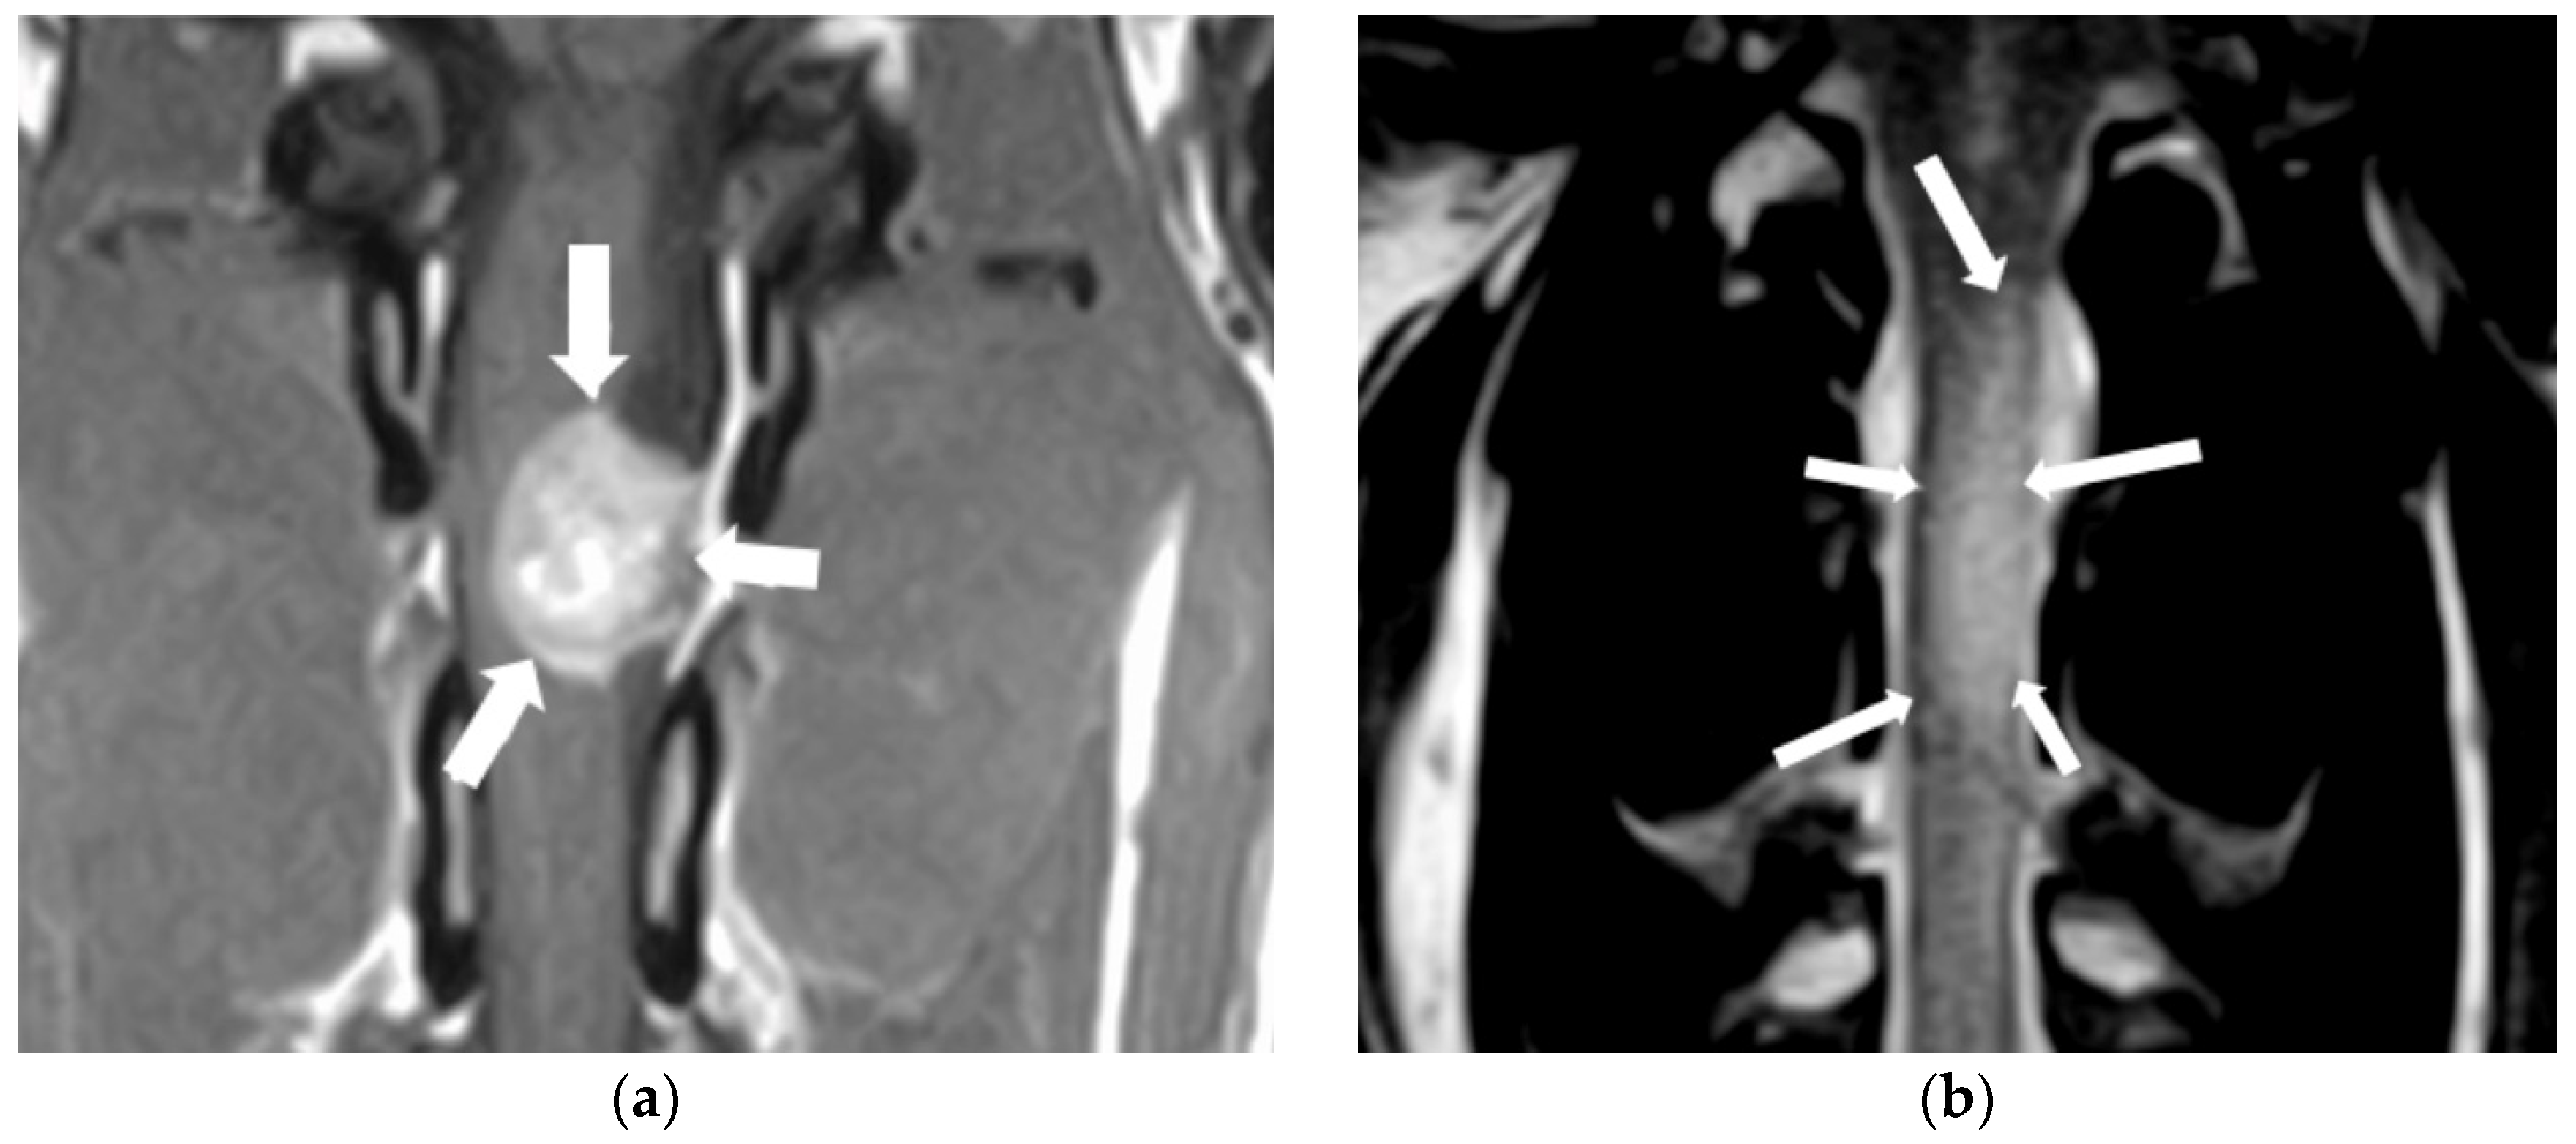

3.3. Spinal Cord Neoplasia